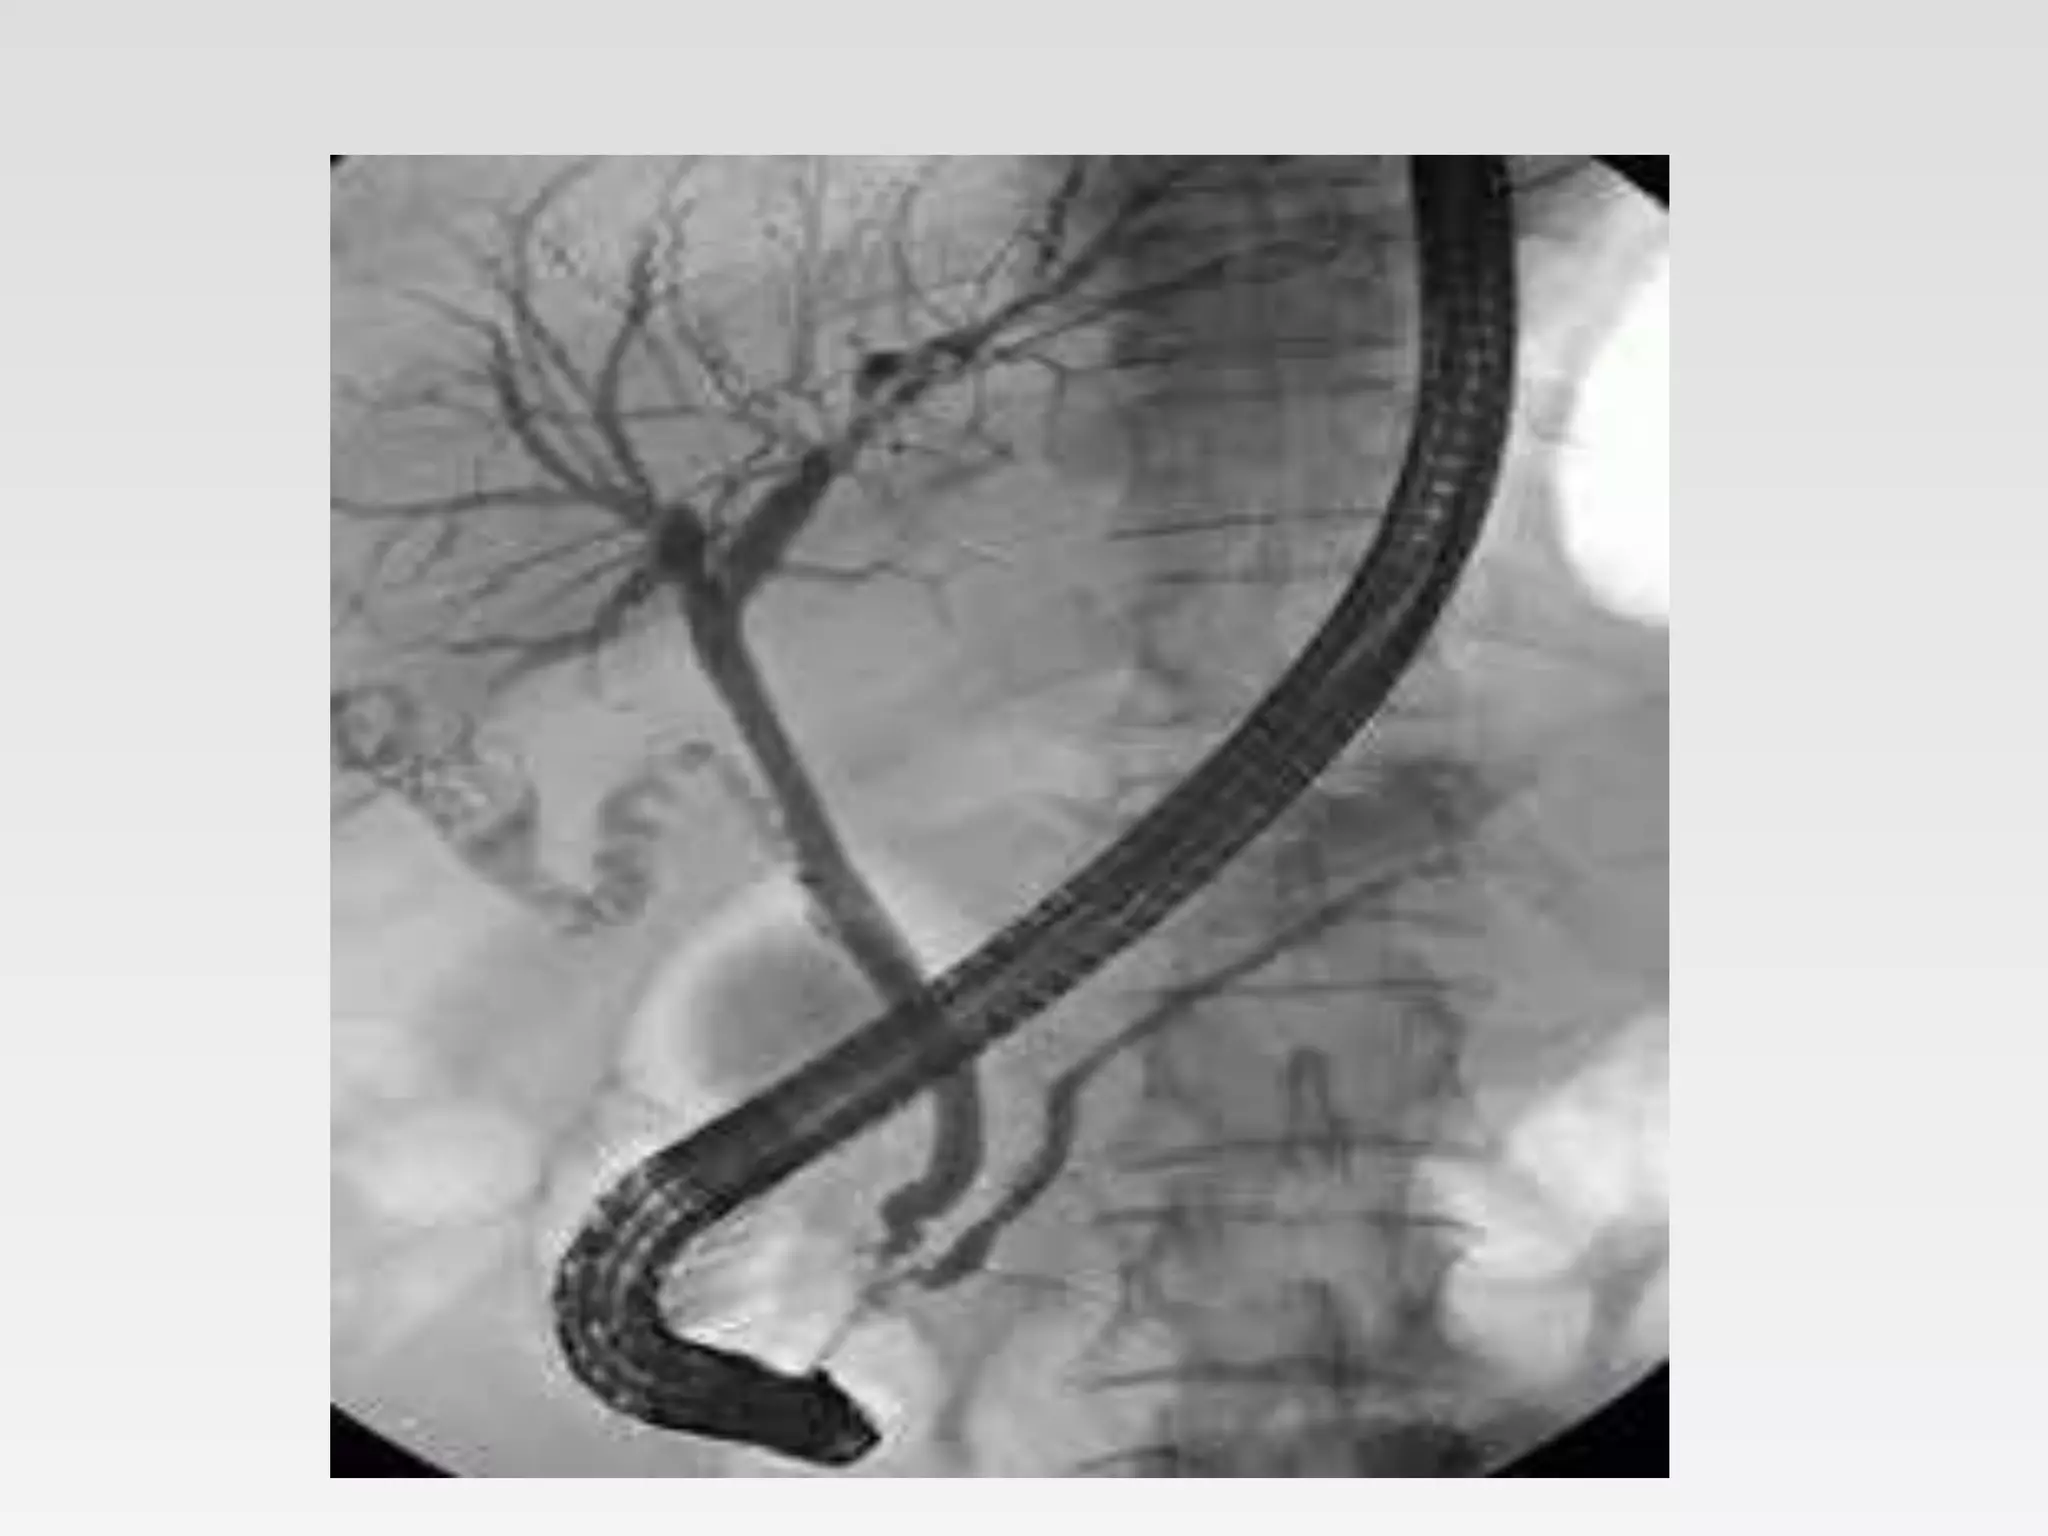

• ERCP endoscopic Retrograde Cholangio-

Pancreaticography

Therapeutic endoscopy • ERCPendoscopic Retrograde Cholangio- Pancreaticography • Endoscopic haemostasis – Injection sclerotherapy – Argon plasma coagulation – Variceal banding – clipping • Dilatation strictures • Polypectomy • Stenting • Percutaneous endoscopic gastrostomy • Foreign body removal